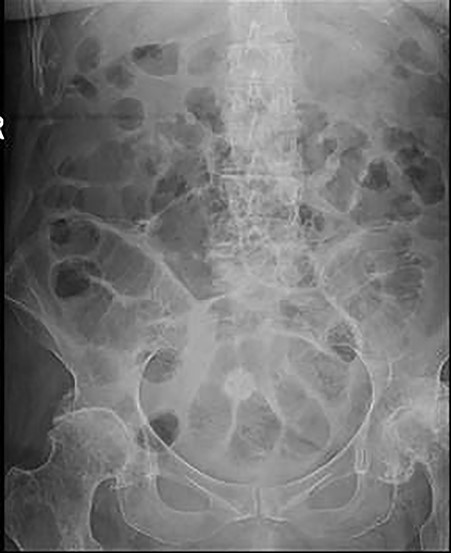

Plain abdominal X-ray demonstrated a calcified lesion on the right as well as distended loops of small bowel (Fig. 1). Abdomino-pelvic contrast CT scan showed an abnormal gallbladder containing pockets of air and a fistulation through the lateral part of D2,with a 22 mm calcified lesion within the ascending colon (Fig. 2a–d). Based on the history, physical examination and CT scan findings, our diagnosis was of resolving gallstone ileus.

Plain abdominal X-ray at presentation demonstrating gallstone as well as distended loops of small bowel.